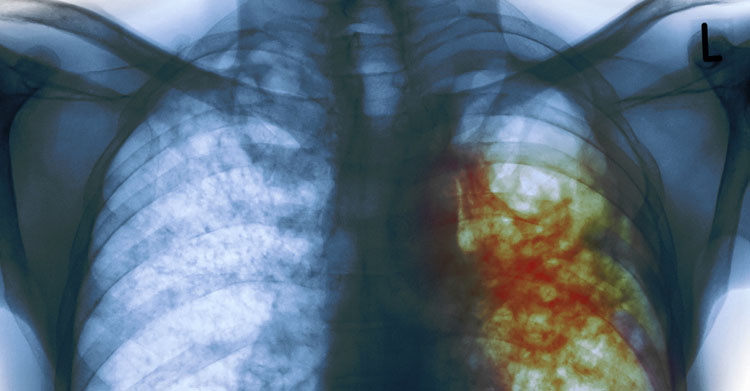

1. Рак

Рак – болезнь, преследовавшая человека, является одной из страшных болезней века. Вызывается множественными причинами, например, радиоактивными излучениями и химическими веществами, к которым относятся органические красители, выхлопные газы, некоторые пищевые консерванты. Хроническая усталость и стресс тоже, как ни странно, запускают процесс роста раковых клеток. Рак может развиваться из-за вирусов папилломы и генитального герпеса, передающиеся половым путём. Так что беспорядочная, незащищённая половая жизнь, которая в наше время достаточно распространённое явление, является серьезным фактором риска.